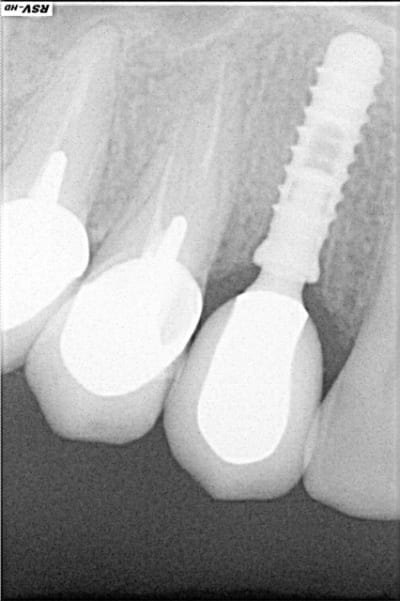

rx à j=0 et j+4 mois

ce qui est surprenant , c'est la présence d'os au niveau du col.